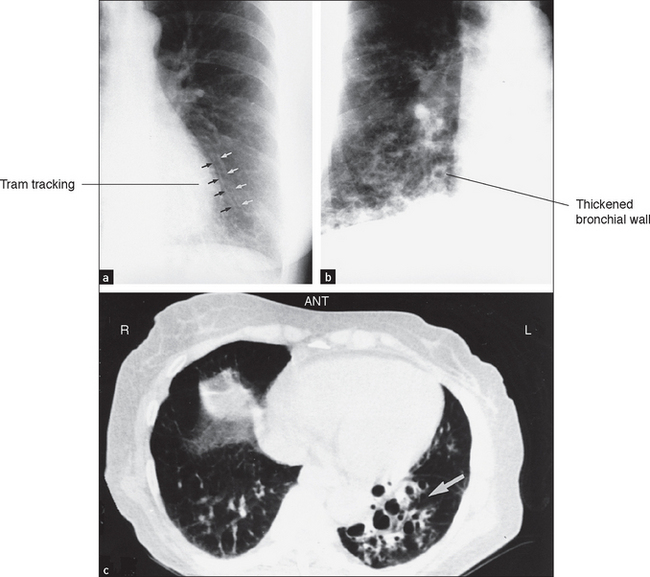

High-resolution CT scans give more detailed information about the lungs but expose the patient to hundreds of times more radiation. They are particularly useful for diagnosing interstitial lung disease, pulmonary haemorrhage (see Figure 12.13) and bronchiectasis (see Figure 12.14). Primary and secondary lung tumours are best imaged with CT and tuberculous involvement of the lungs can be quantified (see Figure 12.15).

Figure 12.14 (a) to (c) Bronchiestasis (From Mettler FA. Essentials of radiology, 2nd edn. Saunders 2005.)